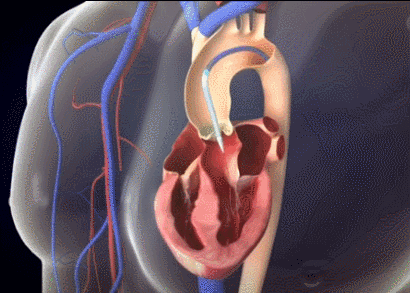

急诊科主任王斌介绍,心脏血液进出有4个重要的阀门,都是瓣膜结构,其中就包括主动脉瓣和二尖瓣。心脏的血液经由主动脉瓣泵入主动脉,进而随着血管分支遍布全身。4个阀门中,主动脉瓣承受的压力最大,因而,主动脉瓣虽然耐用,但长年承受巨大压力还是容易坏掉。主动脉一旦狭窄,心脏的血液就无法顺利泵入主动脉供给全身,将造成严重后果。

但陈奶奶的情况要复杂疑难得多,经检查,她原有的二尖瓣机械瓣与主动脉瓣的位置距离仅2.7mm,一旦瓣膜植入位置不当,会影响原先二尖瓣瓣叶的正常开合,后果不堪设想,这给手术团队带来极大的挑战。

如何能更精准有效地将人工瓣膜微创植入主动脉瓣,且不影响二尖瓣机械瓣的运作呢?华体会体育 王焱院长率团队进行了多次缜密术前讨论,最后决定为陈奶奶采用刚刚上市不久的新型人工瓣膜——可回收Venus A-Plus瓣膜。作为我国首个可回收瓣膜系统,该瓣膜能有效降低复杂手术难度,一旦瓣膜植入位置不合适,还可以回收后再次尝试,让医生在术中能更从容地进行精准定位释放,减少严重并发症的发生,从而降低手术风险,提高成功率。